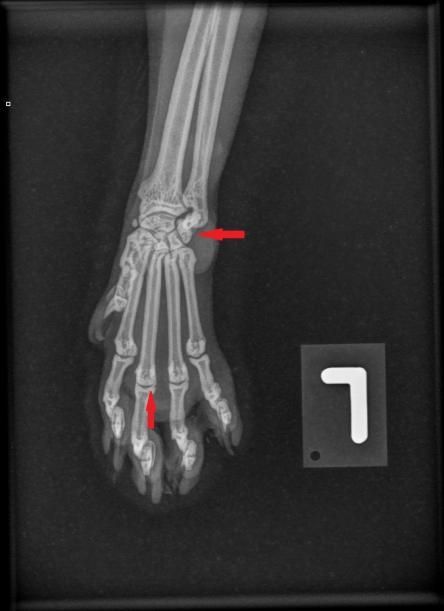

Die Besitzerin berichtet, dass der Kater recht lahmheitsfrei laufe, aber nicht über eine grosse Sprungkraft verfüge. Die Beine von Maxwell sind eher kurz und er scheint hinten und vorne X-beinig. Der Gang der Katze wirkt staksig; eine eigentliche Lahmheit ist nicht zu sehen. Um Aufschluss über die Situation in den Gelenken zu erhalten, werden die Vorderpfoten/Handgelenke, Hinterpfoten/Fusswurzelgelenke und die Wirbelsäule geröntgt. Es ist zu erkennen, dass Hand- und Fusswurzelgelenke gegenüber der Normalsituation eine X-beinigkeit (Valgisierung) aufweisen, an verschiedenen Stellen Anzeichen einer Arthrose vorhanden sind und insbesondere die Mittelhand- und Mittelfussknochen kurz und gedrungen erscheinen. Ein Teil der Fusswurzelknochen von Maxwell sind ausserdem zu einem einzigen Knochen verwachsen.

Vorderpfote links Maxwell Vorderpfote links normale Katze